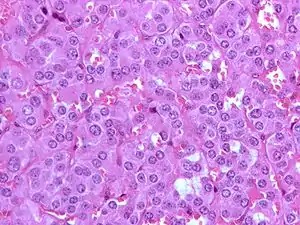

![]() Мікрофотознімок феохромоцитоми (фарбування г-е). Мікрофотознімок феохромоцитоми (фарбування г-е). | |

Мікрофотознімок феохромоцитоми.